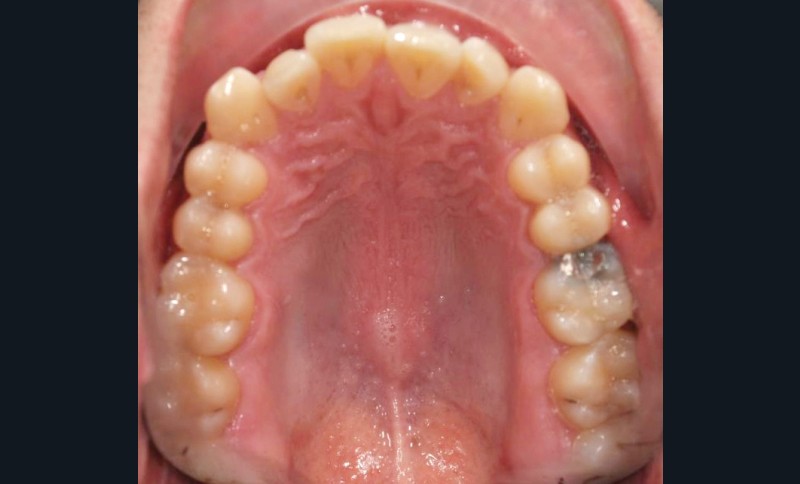

En intra-arcades (fig. 4-6), on note une classe III molaire et canine (fig. 4-5), trois plans d’occlusion, une déviation des milieux d’origine mandibulaire et un inversé articulé du bloc incisif maxillaire ; le biotype parodontal est fin, et l’on note des récessions gingivales (12, 13, 23, 33, 43) certainement dues à la mauvaise position et aux forces mal réparties lors de la mastication (fig. 5). L’arcade maxillaire est carrée avec une DDM antérieure (fig. 7), l’arcade mandibulaire étroite et allongée (fig. 8).